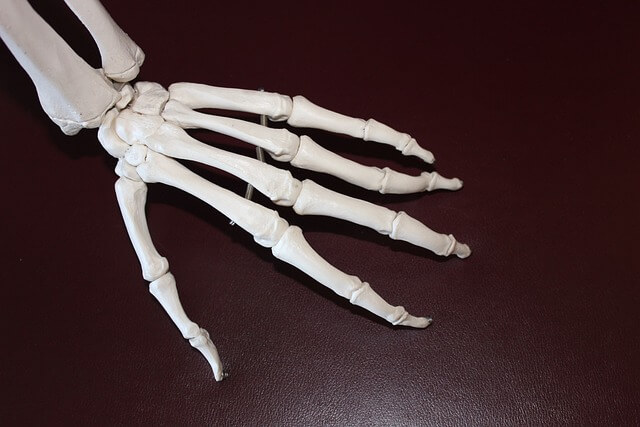

손가락 관절염 증상 및 치료법 ㅣ손가락 관절에 좋은 운동 알아보기

손가락 관절염은 많은 사람들에게 고통을 가져다주는 흔한 질병이고, 손과 손가락을 자주 사용하는 현대인들에게 특히 발생 빈도가 높은데요.

아래글에서는 손가락 관절염이 어떤 문제를 일으키고, 이를 관리하고 치료하는 방법에 대해 알아보겠습니다.